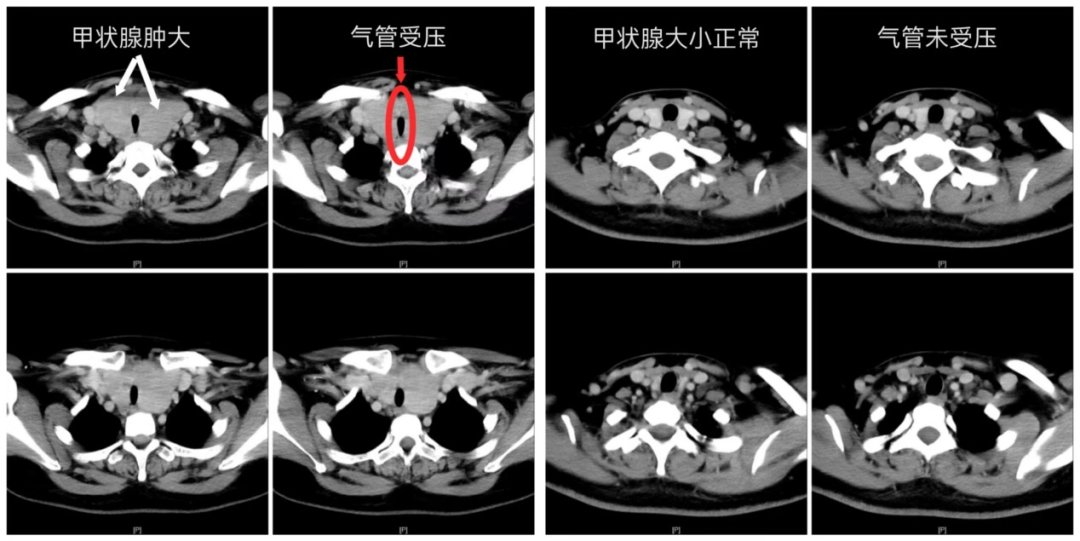

影像检查结果令人心惊

气管被挤压成“细线”

术后6小时,王女士即恢复清晰发声,可自主进食流质食物,四肢活动自如。“呼吸终于不费劲了。”她对着镜子看着平坦的颈部,声音仍带着些许沙哑,却掩不住眼底的欣喜。术后影像复查显示,原本被挤压成“细缝”的气管已恢复通畅,这颗困扰她十余年的“生命腺”重荷被成功卸下。